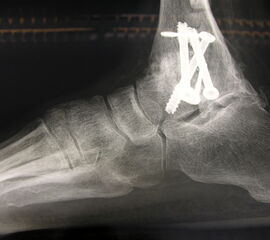

Erreichen eines schmerzfreien oberen Sprunggelenkes mit belastbarem und plantigrad aufsetzbarem Fuss (Abb. 1a und b) unter Verzicht auf die Bewegungsfunktion des oberen Sprunggelenkes. Operative Resektion der arthrotisch veränderten Gelenkflächen bis in den subchondralen frischen Knochen von Tibia und Talus. Fusion mittels Kompressionsschrauben oder Arthrodeseplatten, bedarfsweise Arthrodesenagel.

Abbildung 1a

Abbildung 1b